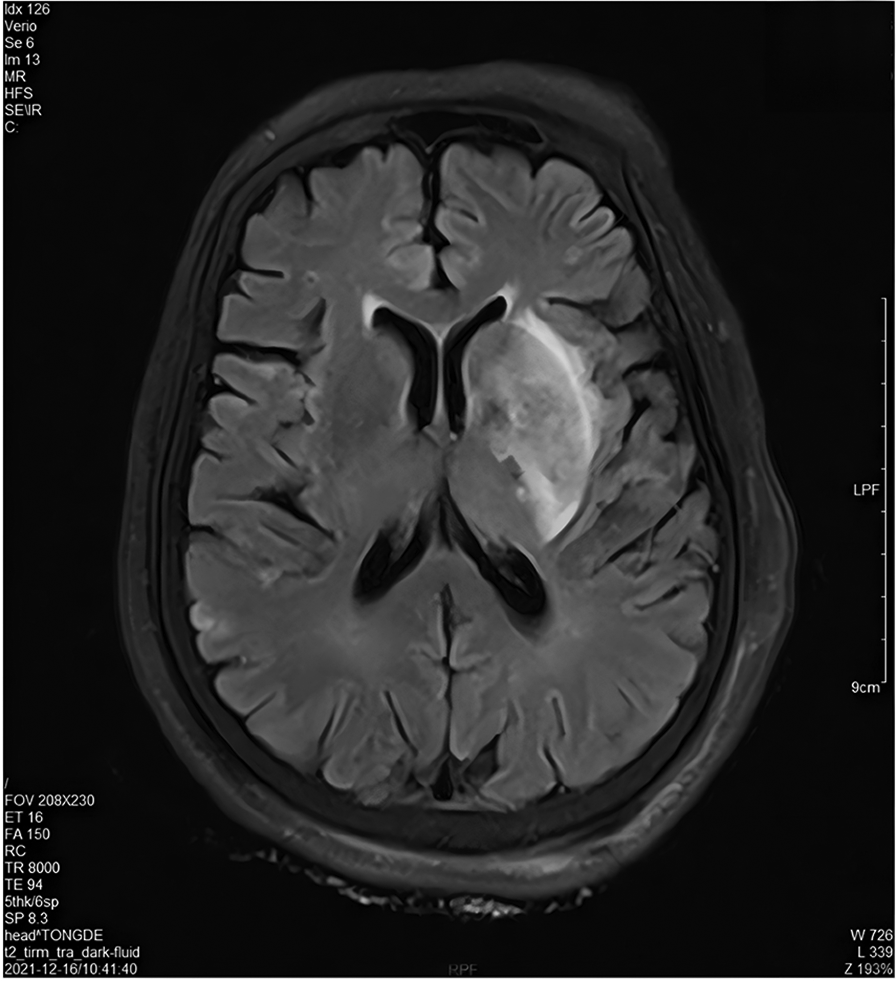

The brain MRI on December 16th showed acute multiple cerebral infarction (Figure 2) (Attachment 3). Concurrently, a right echocardiogram confirmed the presence of RLS, suggesting the existence of patent foramen ovale or an atrial septal defect (Attachment 4). The diagnosis of PDE must meet three criteria: VTE, intracardiac shunt or pulmonary fistula and arterial embolism (12). The diagnosis of PDE is clear based on the above imaging evidence. After the contraindications were eliminated, rivaroxaban was taken orally for anticoagulant therapy, with the dosage of rivaroxaban being adjusted according to renal function. Notwithstanding prior administration of thrombolysis and oral anticoagulation therapy, coagulation function testing revealed persistent augmentation in D-dimer levels and persistent reduction in fibrinogen levels. Concurrently, the ultrasound examination of the lower extremity vasculature revealed the occurrence of new venous thrombosis (Attachment 5). There are many potential risk factors for thrombosis. We perfected the anti-neutrophil antibody combination + antinuclear antibody series (all), immunoglobulin A/G/M, anticardiolipin antibody, anti-β2 glycoprotein and other tests during the treatment, and all of them were negative. Based on the analysis of the diagnosis and treatment standards for VTE, the medical team believed that the patient may be complicated with thrombophilia. Hence, we added the detection of thrombophilia gene. In this paper, matrix-assisted laser desorption ionization time-of-flight mass spectrometry (MALDI-TOF) was used to detect 9 thrombogenic genes (PROC, PROS1, SERPINC1, F2, F5, HRG, THBD, PAI-1, MTHFR) and 27 hot spot variations. The detection of thrombus-prone genes revealed a thrombophilic risk factor: plasminogen activator inhibitor-1 (PAI-1) (4G/4G) (Attachment 6).

Figure 2

Cranial MRI on December 16, 2021.